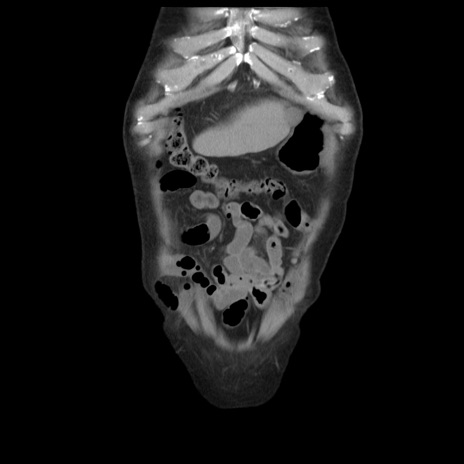

症例21(冠状断像)

【症例】70歳代男性

【主訴】腹痛

【現病歴】肝硬変・肝細胞癌にてかかりつけの方。約9時間前に食後より腹痛出現。症状が徐々に増悪し、嘔吐出現したため来院。

【既往歴】肝硬変、肝細胞癌(RFA、TACE後)

【身体所見】意識清明、表情苦悶様、BT 36℃、BP 129/78mmHg、P 88bpm、SpO2 97%(RA)、右上腹部から心窩部にかけて圧痛あり、反跳痛なし、筋性防御あり。

【データ】WBC 5800、CRP 0.16